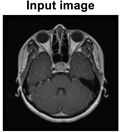

A growth that may adversely impact a person’s life is a brain tumor, which can appear in the tissues enclosing the brain or skull. Two characteristics can identify a benign or malignant growth. While secondary tumors, also referred to as brain metastasis tumors, are typically formed from tumors outside the brain, primary cancers start inside the brain. Meningiomas, pituitary adenomas, and gliomas are the three most common primary brain tumors. The brain and spinal cord membrane layers are the origin of meningiomas, a type of tumor that grows slowly. Cancerous cells that arise in the pituitary gland are referred to as pituitary adenomas [1]. The brain tissue is compressed by the irregular growth of these tumors. Malignant tumors, in comparison with benign tumors, grow unevenly and damage the tissues around them. Surgical techniques are frequently employed in the treatment of brain tumors [2]. Because MRI is non-interfering, it is preferred over computed tomography (CT), positron emission tomography (PMT), and x-rays [3]. It is estimated that 79,340 Americans aged 40 and older will be diagnosed with a primary brain tumor by 2023. It is estimated that one million Americans suffer from primary brain tumors; of these, 72% are benign tumors and 28% are malignant. The adults with primary brain tumors typically have meningioma (46.1%), glioblastoma (16.4%), and pituitary tumors (14.5%) [4,5]. Biopsies are taken for analysis after the tumor is found using standard medical techniques like MRI. The first test used in medicine to find cancer is MRI [6,7]. Two MRI pictures of two distinct brains are shown in Figure 1.

Figure 1. MRI scans performed on two different brains. (a) On the left is a tumor, and (b) on the right is a healthy brain [8].